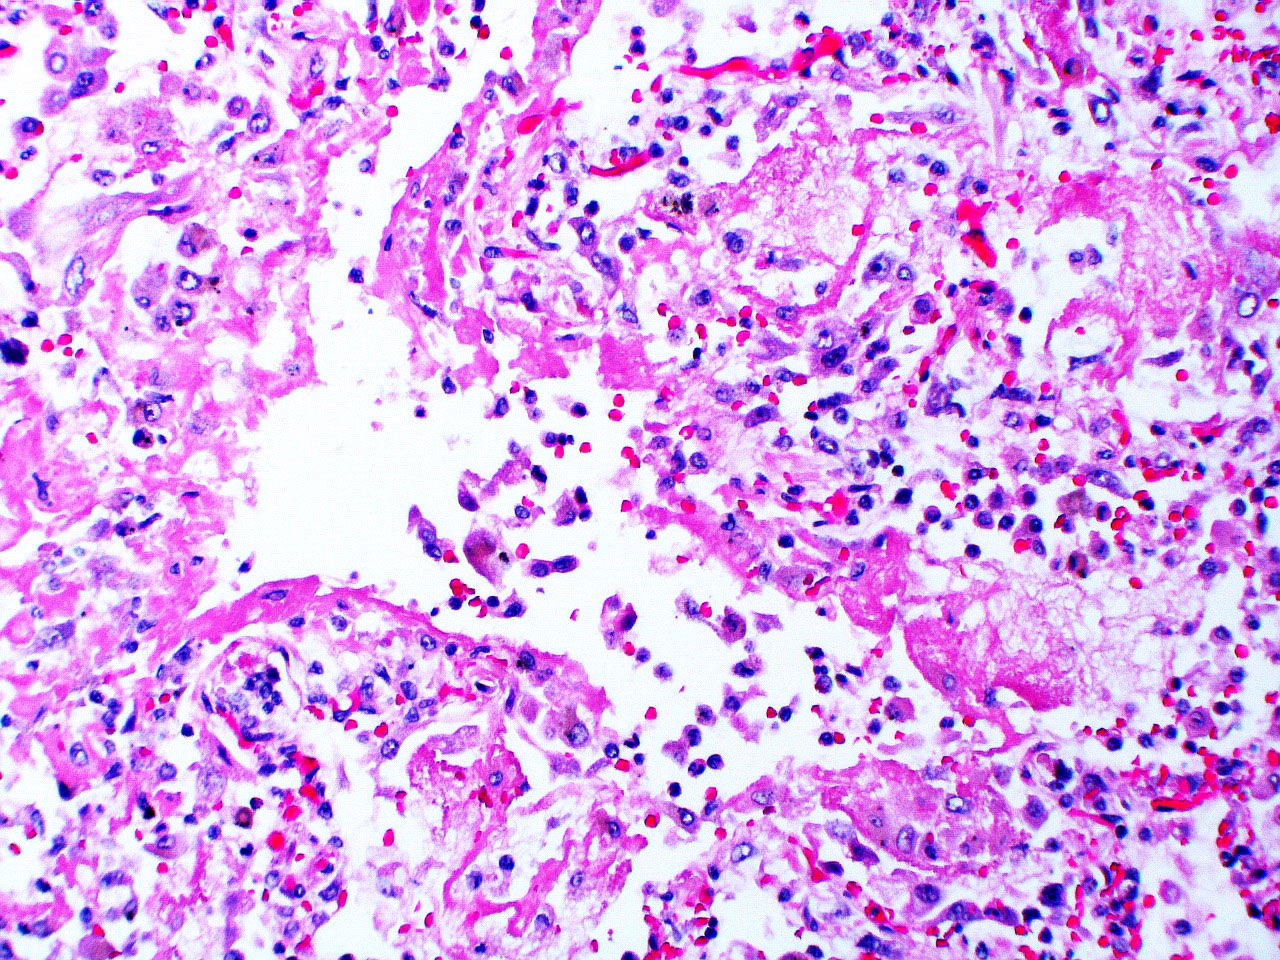

Microscopic (histologic) description

- Histopathology of DAD progresses from exudative (acute) phase through proliferative / organizing (subacute) phase to chronic fibrotic phase roughly corresponding to the period of ARDS (Am J Pathol 1976;85:209, Arch Pathol Lab Med 2010;134:719, Clin Chest Med 2000;21:435, N Engl J Med 2000;342:1334)

- Exudative (acute) phase

- Alveolar change

- Hyaline membranes on alveolar duct or sacs

- Interstitial and intra-alveolar edema

- Collapsed alveoli

- Epithelial change

- Denudation and necrosis of type I pneumocytes

- Vascular change

- Necrosis of endothelial cells

- Neutrophil aggregation

- Microthromboemboli

- Hemorrhage

- Alveolar change

- Proliferative / organizing (subacute) phase

- Alveolar change

- Remnants of hyaline membrane with or without organization

- Interstitial and intra-alveolar proliferation of myofibroblasts

- Lymphocytic infiltration

- Epithelial change

- Proliferation / hyperplasia of type II pneumocytes

Microscopic (histologic) images

Contributed by Akira Yoshikawa, M.D. and Yale Rosen, M.D.